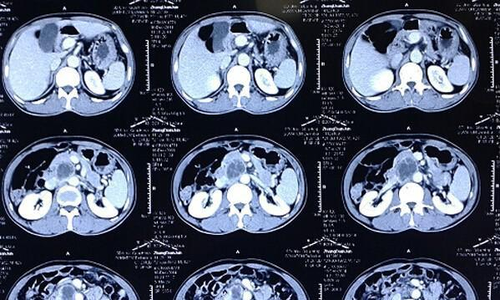

现代医学需要利用医疗技术来检查医生肉眼看不到疾病。b超和x光是常见的检查项目,x光和b超是两种不同的概念,两者是有区别的。那么,x光和b超的区别一样吗?

x线、b超这些常用的影像学检查区别是不一样的。孕妇在孕检的时候需要做b超检查确认宝宝生长发育情况,但是孕妇是不能做x光检查的。x光的穿透性比较强,能穿透人体的组织结构。可以用x射线检查来识别各种组织,根据组织阴影的形态和浓淡变化来分析是否正常。

b超的原理是用振动频率每秒在20000次以上、超过入耳听觉阈值上限的超声波穿透人体,当声波遇到人体组织时会产生反射波,通过计算反射波成像,借此进行疾病的诊断。超声检查无刨伤、无痛苦、无电离辐射,是许多内脏、软组织器官检查的首选方法,在早期妊娠诊断、体检和防癌普查等方面也被广泛使用。